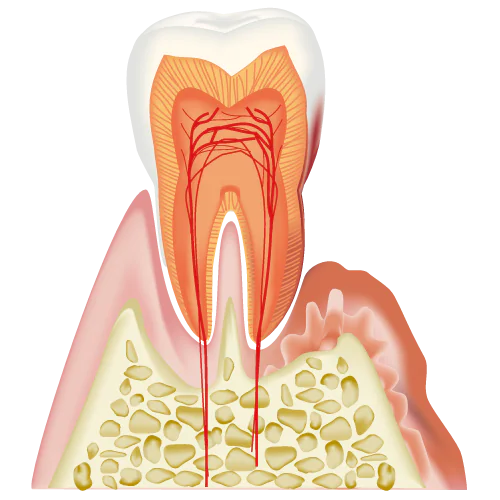

歯周病は歯周組織が歯垢(プラーク)に含まれている歯周病菌に感染し、歯肉の腫れや出血、最終的には歯の喪失につながる疾患です。初期段階では自覚症状がほとんどないため、多くの人が気づいていません。しかし、成人の約8割が歯周病にかかっているとされ、日本人にとって最も一般的な歯の喪失原因の一つです。

歯周病は歯周組織が歯垢(プラーク)に含まれている歯周病菌に感染し、歯肉の腫れや出血、最終的には歯の喪失につながる疾患です。初期段階では自覚症状がほとんどないため、多くの人が気づいていません。しかし、成人の約8割が歯周病にかかっているとされ、日本人にとって最も一般的な歯の喪失原因の一つです。

歯周病の主な原因はプラークと呼ばれる歯垢です。プラークは歯と歯ぐきの間に形成され、乳白色の粘性のある物で、中には歯周病やむし歯の原因となる細菌が集まっています。

1mgのプラークには約10億もの細菌が含まれているとされています。時間の経過とともに、プラークはバイオフィルムとして強固な集合体へと変化します。

このバイオフィルムは唾液の殺菌作用を避け、歯周病やむし歯の進行を促進します。歯垢の効果的な予防と管理は、歯科衛生の基本であり、日常的な歯磨きや定期的な歯科検診が重要です。